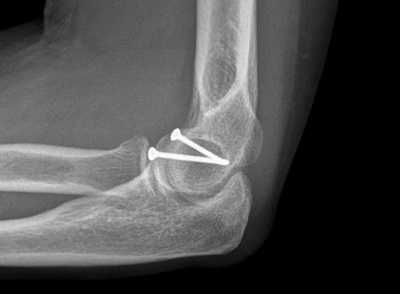

Наилучшим методом лечения внутрисуставного перелома локтевого отростка, позволяющим сохранить движения в суставе - это остеосинтез (устранение смещения и фиксация отломков металлоконструкцией). Операцию выполняют сразу после поступления пациента. Это ускорит реабилитацию и позволит сохранить полный объем движений в локтевом суставе. Локтевой сустав очень капризный в плане реабилитации. Если иммобилизация продолжается 4 недели и более, то практически во всех случаях у взрослых пациентов развивается контрактура.то есть движения ограничены на всю жизнь. Если перелом локтевого отростка произошел одним фрагментом, то возможна классическая операция, одна из самых простых и надежных методик - остеосинтез локтевого отростка по Веберу. Выполняется она при помощи двух титановых спиц и титановой проволоки.

До операции:

После операции:

Открытая репозиция и внутренняя фиксация. Это наиболее распространенный метод лечения переломов локтевого отростка. Во время такой операции костные фрагменты сопоставляются друг с другом и фиксируются в нормальном положении винтами, проволокой, спицами или металлическими пластинами.

Ниже представлены некоторые наиболее часто применяемые методы фиксации локтевого отростка.

Фиксация перелома локтевого отростка спицами и стягивающей проволочной петлей

(Слева) Для фиксации перелома локтевого отростка можно использовать один винт, который вводится в костномозговой канал. (Справа) Фиксация перелома пластиной и винтами.